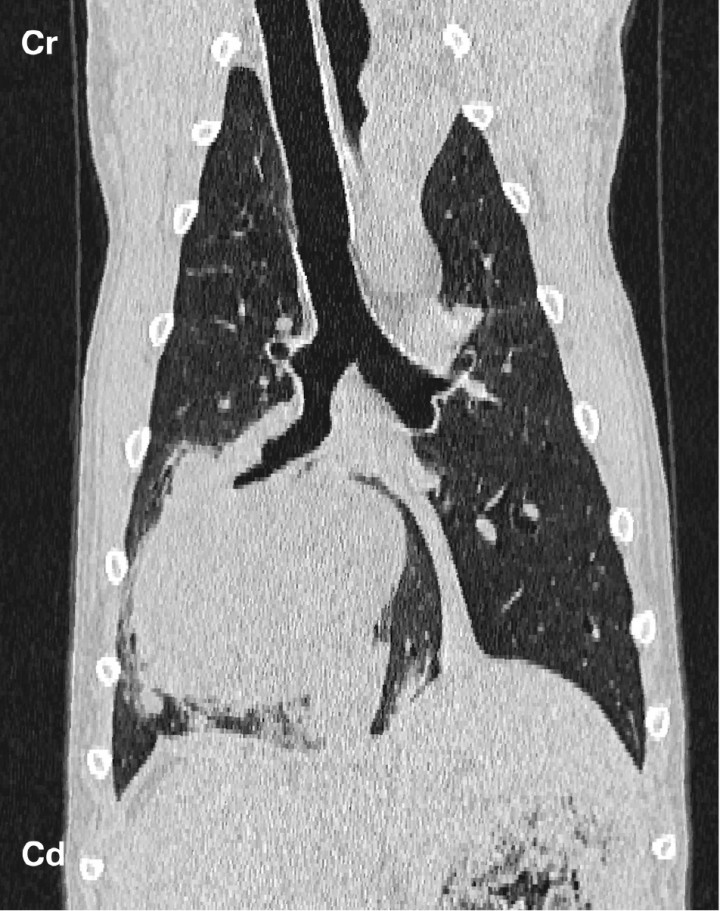

Common mediastinal tumors in dogs and cats include thymoma, heart base tumors, and lymphoma. Other tumor types in this region include thyroid carcinoma, carcinomas of other origin, sarcomas, and mesothelioma. CT evaluation of these tumors is generally nonspecific; however, thymomas are often quite large causing significant mass effect over the adjacent lung lobes, trachea and mediastinal vascular structures, and can extend caudally mainly along the left hemithorax. They can show cystic areas and a solid component with a heterogeneous contrast uptake pattern (Fig. 6).[ Yoon J, Feeney DA, Cronk DE et al.: Computed tomographic evaluation of canine and feline mediastinal masses in 14 patients. Vet Radiol Ultrasound 2004; 45:542-546. [PubMed] ] An important reason for imaging cranial mediastinal neoplasms is to determine the presence and extent of vascular invasion, which can determine operability and prognosis.[ Scherrer W, Kyles A, Samii V et al.: Computed tomographic assessment of vascular invasion and resectability of mediastinal masses in dogs and a cat. N Z Vet J 2008; 56:330-333. [PubMed] ]

<p>(A) Transverse and (B) dorsal reformatted soft tissue window post contrast images of a 6 year-old European Shorthair cat. At the level of the cranioventral mediastinum there is a large, mildly heterogenous contrast enhancing mass (white arrow) with a large cystic area (white asterisk) causing displacement of vascular cranial mediastinal structures to the right and dorsal and caudal displacement of the cardiac silhouette. The mass was consistent with a thymoma. R: right. Cr: cranial. Cd: caudal.</p>

(A) Transverse and (B) dorsal reformatted soft tissue window post contrast images of a 6 year-old European Shorthair cat. At the level of the cranioventral mediastinum there is a large, mildly heterogenous contrast enhancing mass (white arrow) with a large cystic area (white asterisk) causing displacement of vascular cranial mediastinal structures to the right and dorsal and caudal displacement of the cardiac silhouette. The mass was consistent with a thymoma. R: right. Cr: cranial. Cd: caudal.